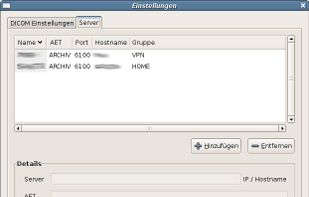

Aeskulap is a medical image viewer capable to load a series of special images stored in the DICOM format for review, query and fetch DICOM images from archive nodes (also called PACS) over the network.